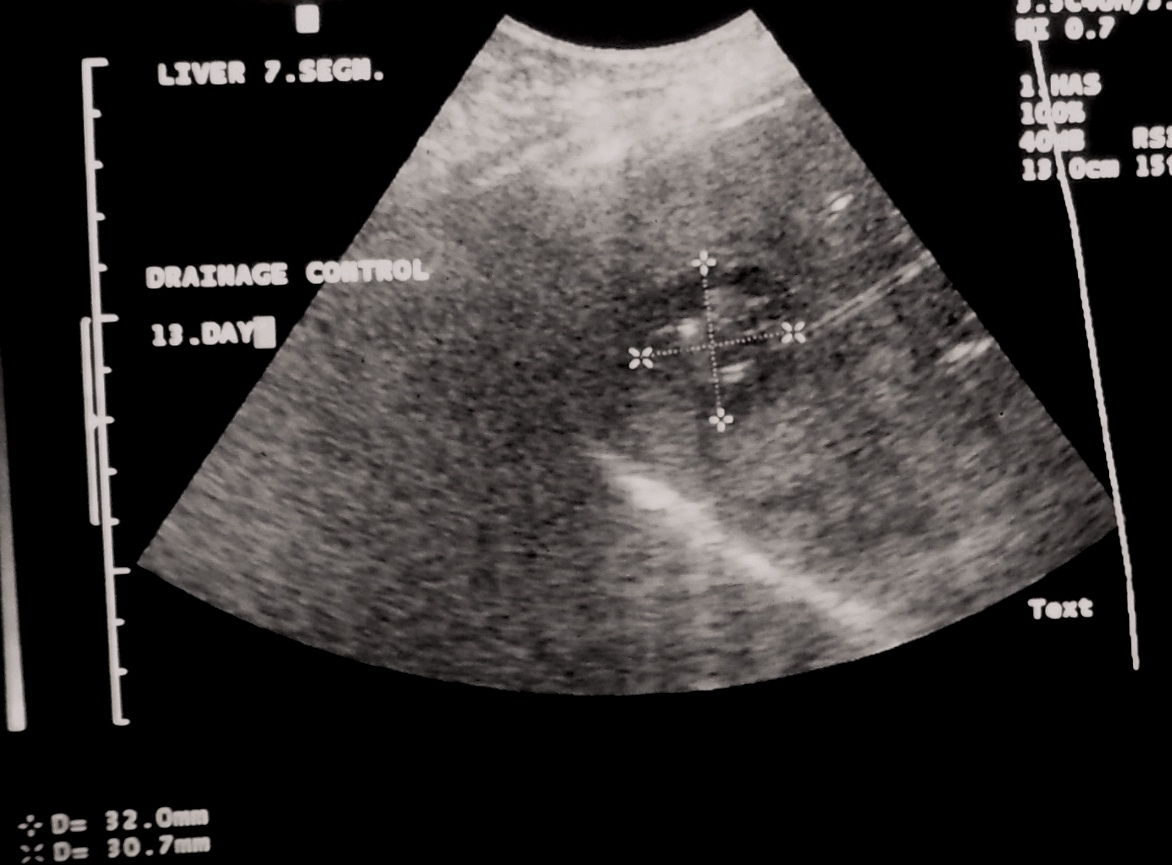

19.2.3.2. Trocar method drainage

During the trocar method both the puncture cannula and the trocar sheath (drain) are inserted together to the lesion with the proper image guidance. After the desired positioning of the trocar the cannula is removed and the sheath stays in the lesion to drain the fluid collection or the abscess. (Figure 10.) The drain is uausally attached to the skin a stitch.

Abscess healing can be accelerated by repeated drainage and lavage of the contents of the abscess. (Figure 11.)

Image

Figure 11. – US guided hepatic abscess drainage control (day 13, after several rounds of lavage and cleaning of the abscess)

The length of the percutaneous drainage is influenced by the washout of the contents and the reduction of its size.